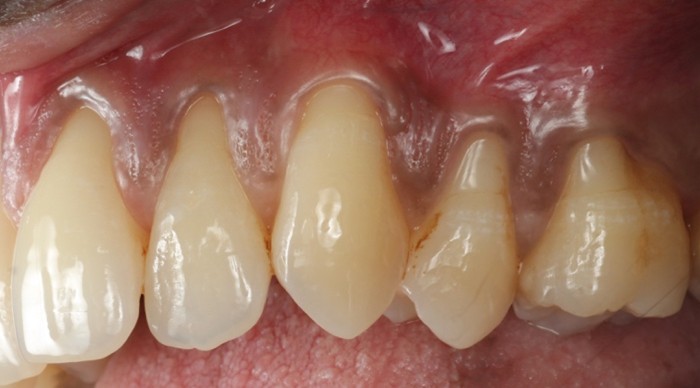

![]() | ![]() |

| Free gingival graft surgery’ to thicken gum and prevent further recession | Gum recession surgery in an aesthetic site |